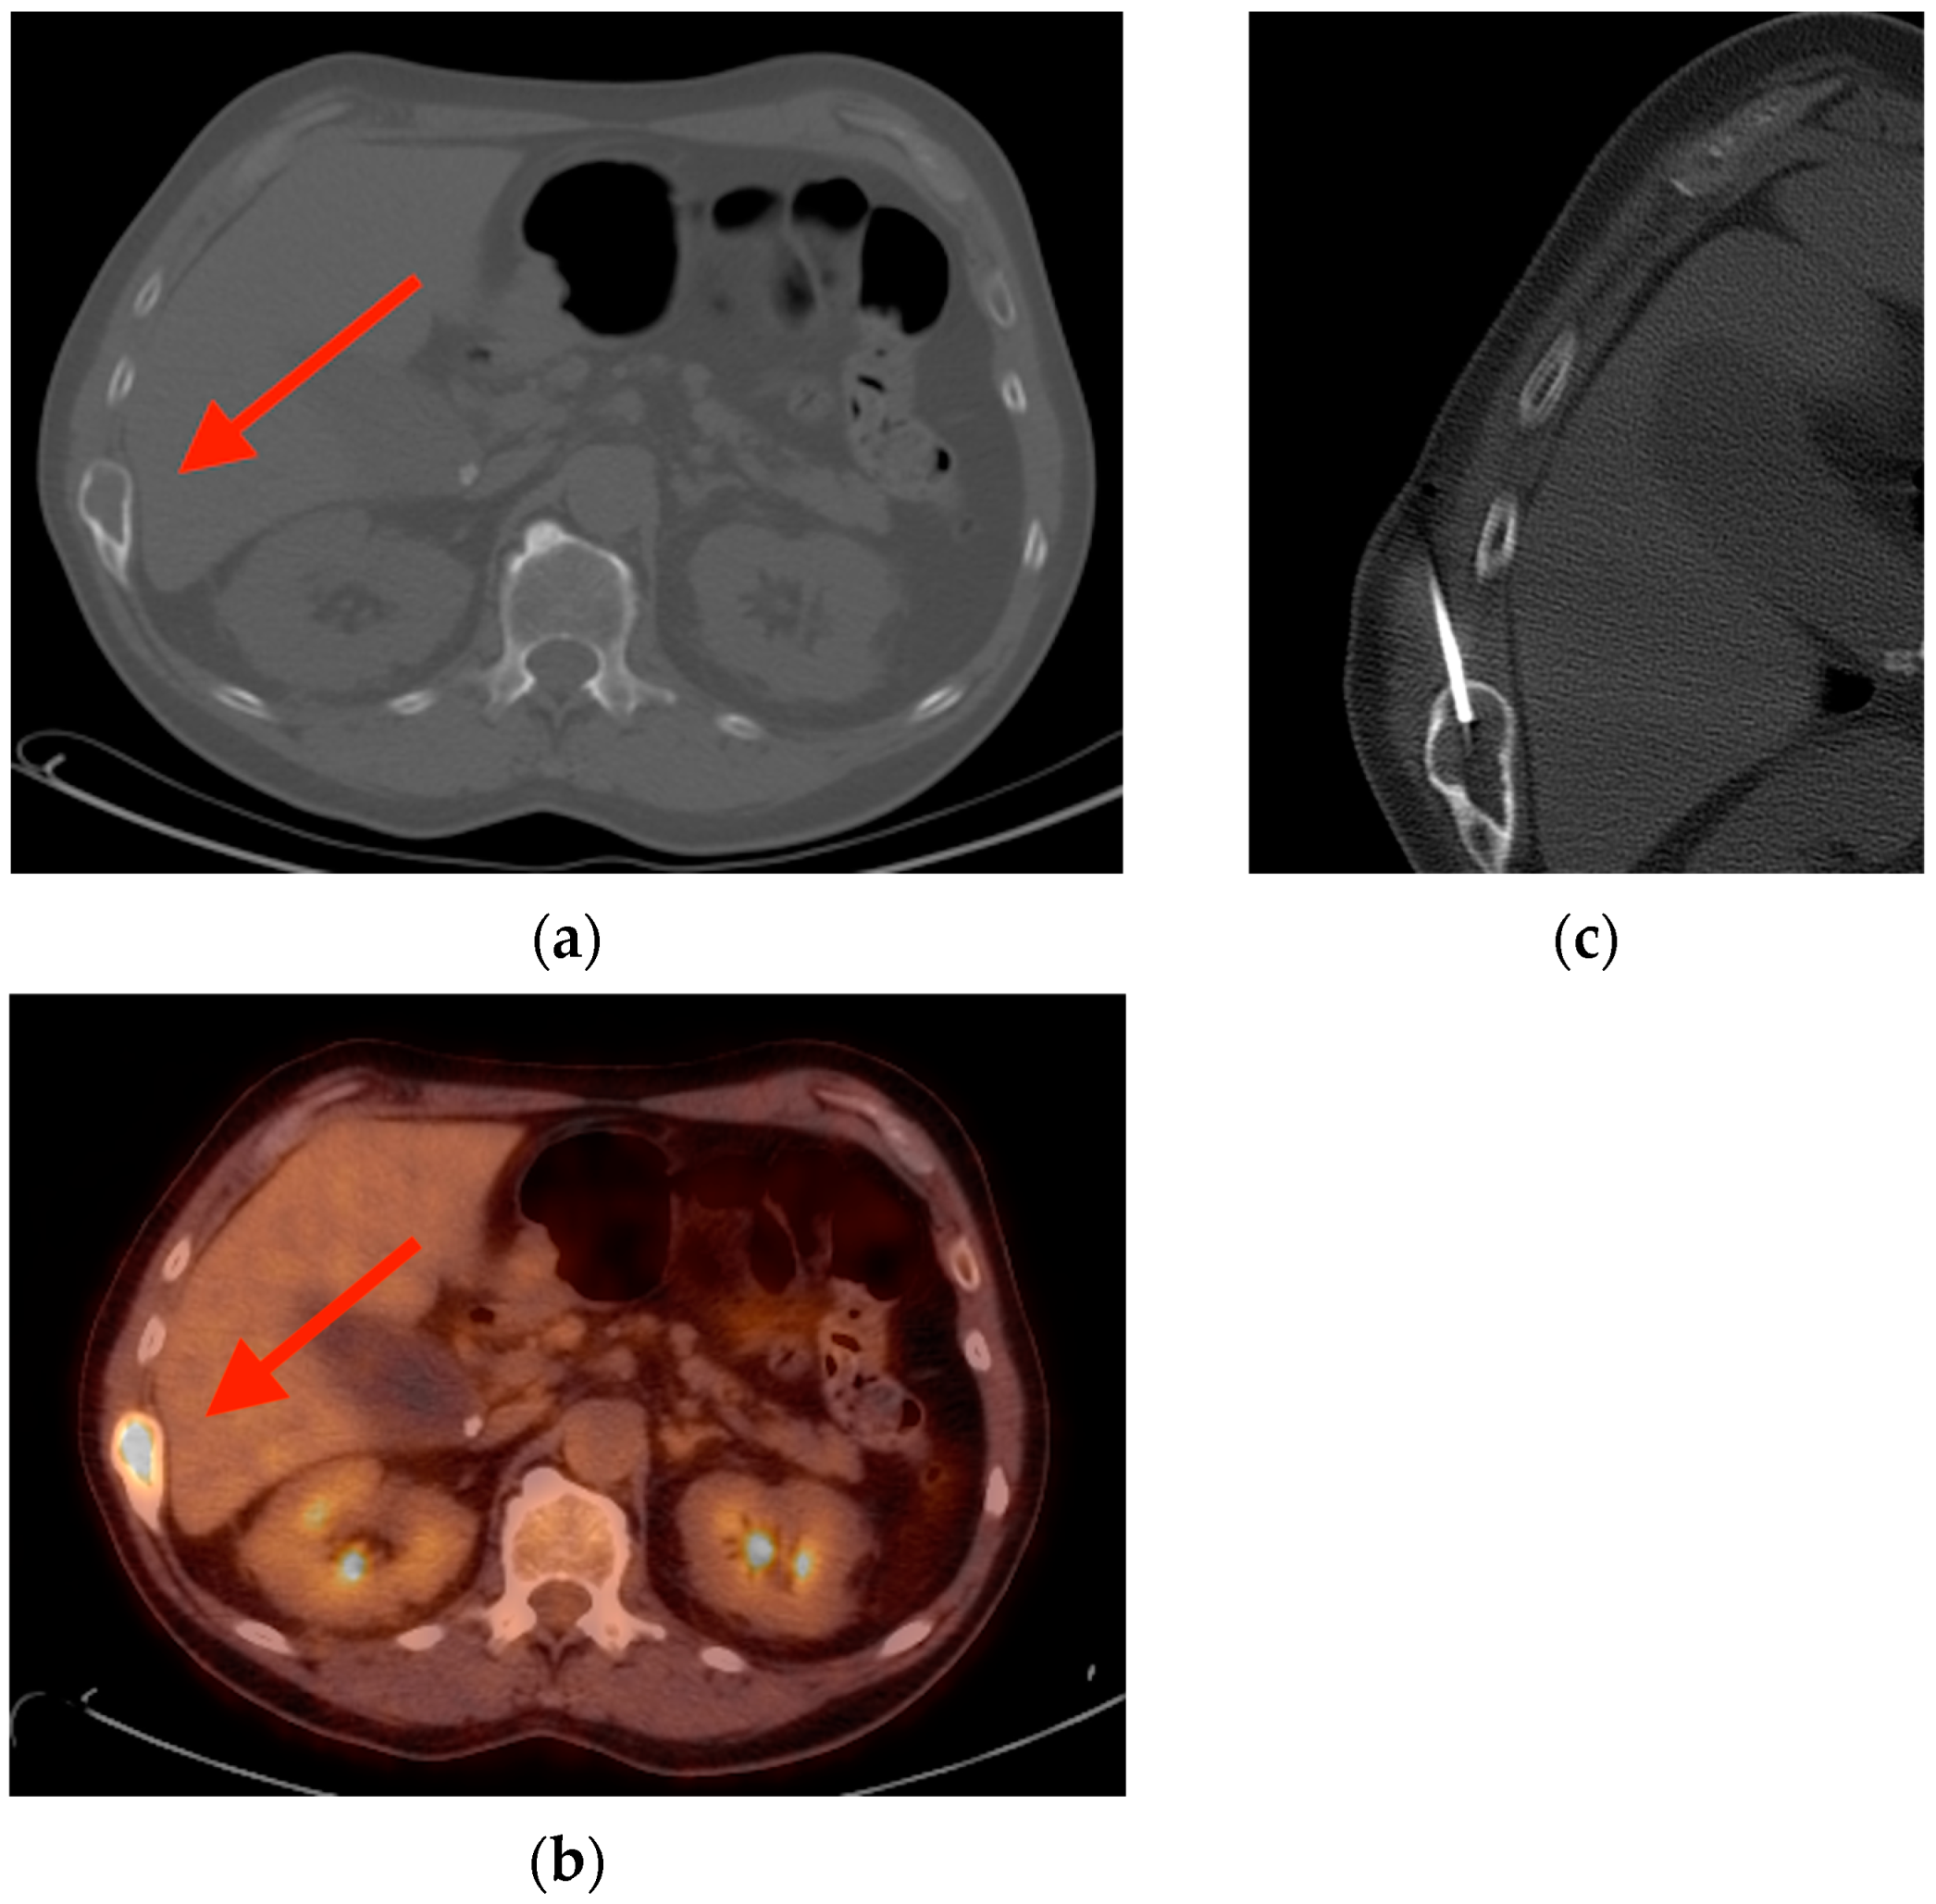

5.1. Fat Necrosis